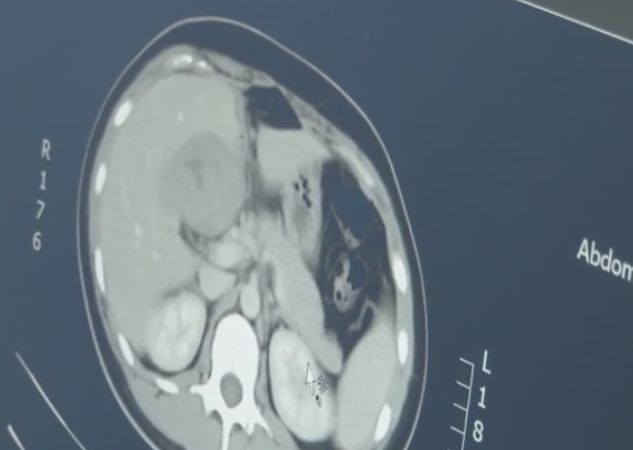

有明显的怀孕指征却找不到孕囊,医生怀疑出现了宫外孕,于是为患者做了CT检查,结果发现,这是一个罕见的宫外孕病例,胚胎跑到了肝脏部位。

据介绍,宫外孕常见于输卵管附近,胚胎跑到肝脏部位极为罕见,很容易引发大出血,危及生命。

医生介绍,如果碰到大的血管,尤其肝门部位,可能短期内就会有几千毫升的失血性休克。